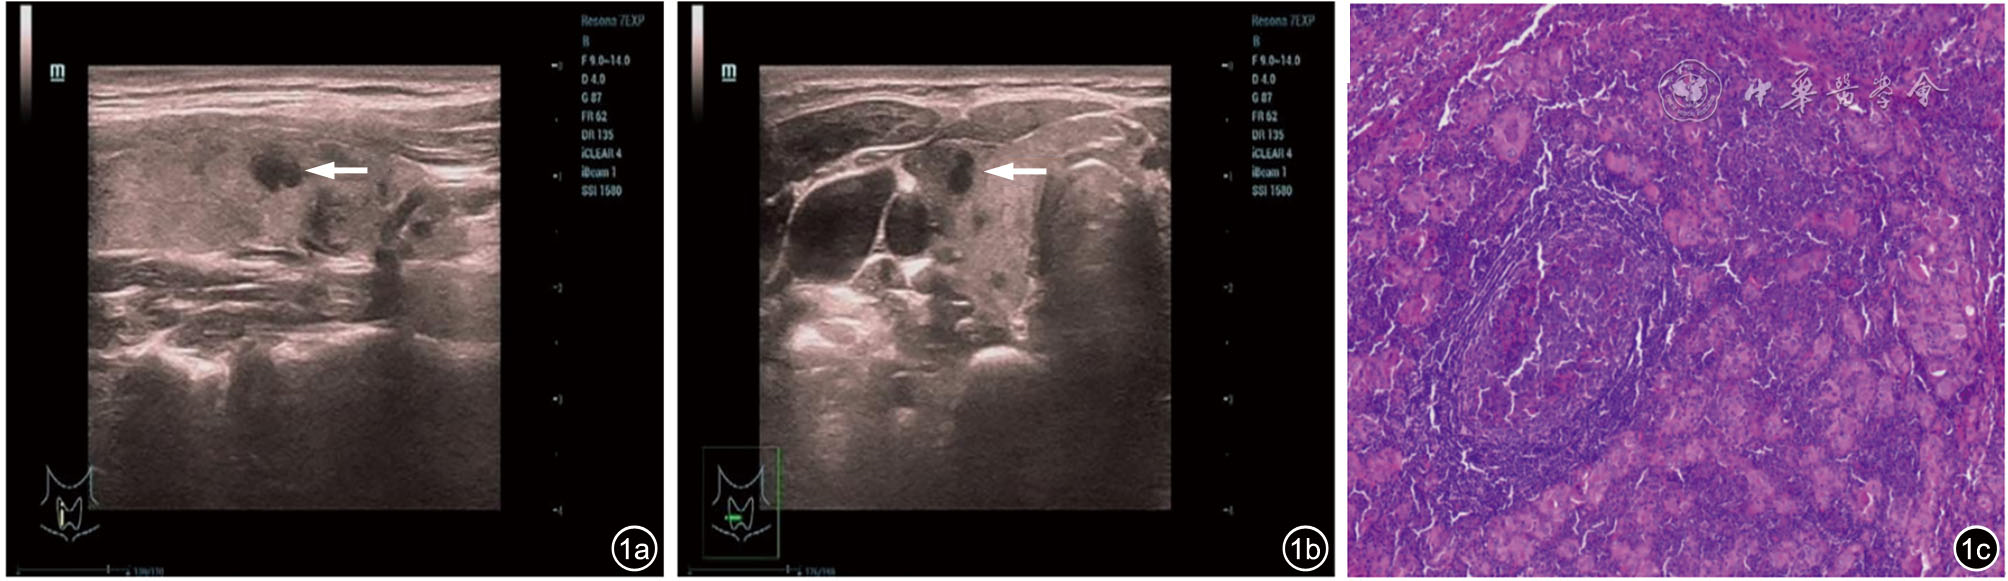

Diagnostic performance of ACR TI-RADS versus C-TIRADS for thyroid micronodules

To compare the diagnostic value of the American College of Radiology thyroid imaging reporting and data system (ACR TI-RADS) and Chinese thyroid imaging reporting and data system (C-TIRADS) in thyroid micronodules.

A total of 1213 patients with 1599 thyroid micronodules confirmed by surgical pathology were enrolled. According to the ACR TI-RADS and C-TIRADS, thyroid micronodules were evaluated and scored. Using surgical pathology as the golden standard, a ROC curve was constructed to determine the optimal cut-off value. Nodules with scores above the cutoff were classified as malignant, while those below as benign. The diagnostic efficacy of ACR TI-RADS and C-TIRADS systems for thyroid microcarcinomas was then analyzed and compared by DeLong test.